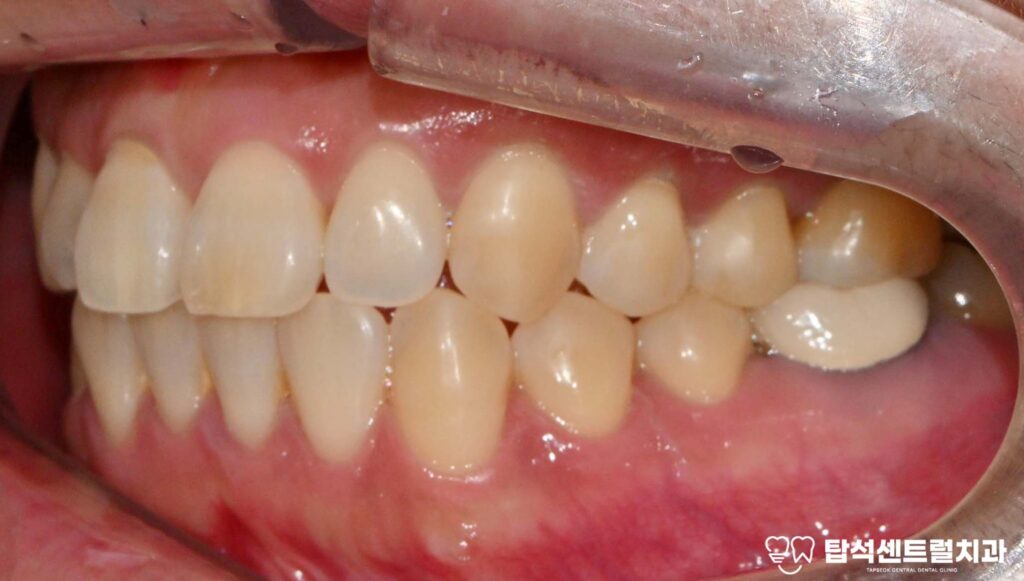

케이스의 경우에는, 아래턱에

임플란트를 식립할 예정입니다.

잇몸뼈의 상태를 확인한 모습입니다.

잇몸 뼈가 남아 있는 양에 따라,

뼈이식의 필요 유무가 정해집니다.